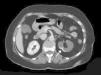

The extent of ischaemic injury was estimated in each patient by dividing the kidney into six segments, such that ARI of the renal poles, with no involvement of the rest of the kidney or the contralateral kidney, was considered to have 1/6 degree of damage (17%) (Figs. 1 and 2). Thus, the estimated injury extent for each patient could theoretically range from 1/6 (17%) to 6/6 (100%).

Estimated mean extent of ischaemic damage measured by CT scan was 35% (2/6 of the total renal parenchyma), with peripheral wedge-shaped hypoperfusion present in 70% of cases, global involvement in 21% of cases and multifocal involvement in 9% of cases. All patients had two native kidneys and there were no cases of previously reported renal atrophy. No differences were found between the subgroups in terms of predominant involvement of the left or right kidney (Table 1).

A contrast-enhanced CT scan reveals perfusion defects, sometimes accompanied by cortical rim sign, which correspond to the blood flow through collateral arteries19 (Fig. 2). If, intravenous contrast is not used, ARI may not be recognised.20